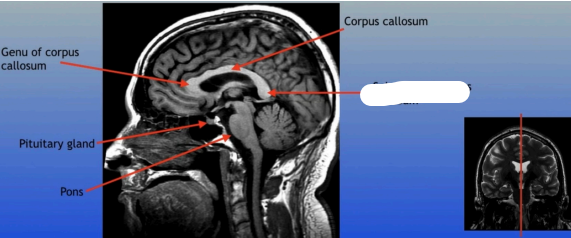

Genu of Corpus Callosum

Pituitary Gland

A small pea-sized gland located at the base of the brain, often referred to as the "master gland" because it regulates many bodily functions through hormone secretion.

Pons

A round structure located above the medulla oblongata and below the midbrain, it acts as a relay station for signals between the cerebellum and cerebrum, and plays a role in regulating sleep and arousal.

Corpus Callosum

Splenium of Corpus Callosum